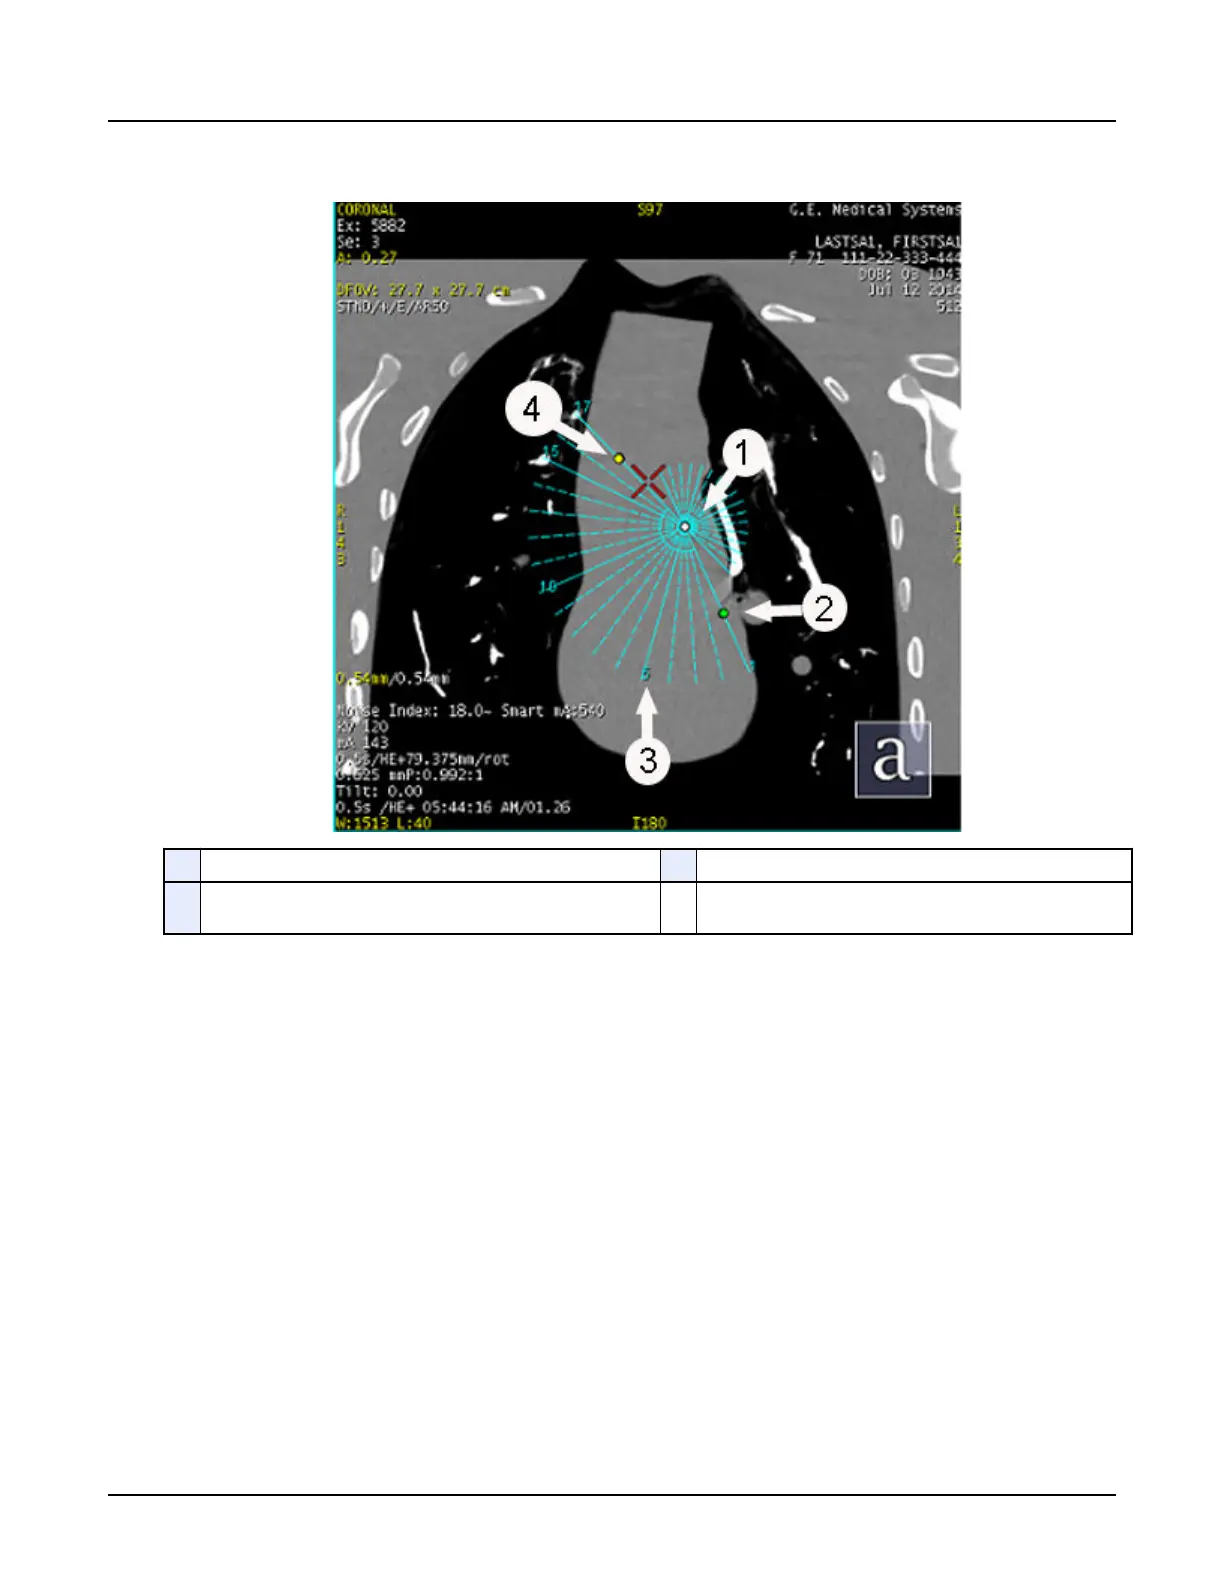

Illustration 16: Graphic object – rotate reformats

1 Handle to move the entire reformat plan 3 Numbers showing start and end of reformat

2 Handle to change the angle between the slices 4 Handle to change the range of numbers between start and

end of reformat